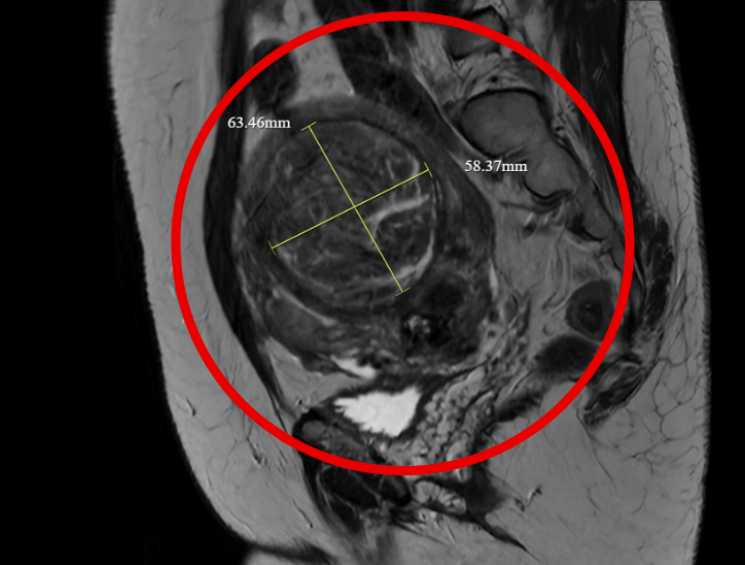

Kết quả kiểm tra tại Bệnh viện Đa khoa Hồng Ngọc cho thấy, chị Hà có tử cung to bất thường, kích thước tương đương thai 6 tháng với nhiều u xơ tử cung, khối lớn nhất 7cm. "Khi tiếp nhận, người bệnh ở trong tình trạng xanh xao, niêm mạc nhợt nhạt - triệu chứng điển hình của tình trạng thiếu máu do rong kinh.

Hình ảnh siêu âm và chụp cộng hưởng từ cho thấy các khối u xơ chèn ép vào nhiều cơ quan, đặc biệt là bàng quang và trực tràng dẫn đến tình trạng căng tức khó chịu", ThS.BS Đỗ Huy Hoàng, Khoa Chẩn đoán hình ảnh và Điện quang can thiệp, Bệnh viện Đa khoa Hồng Ngọc - Phúc Trường Minh cho hay.

Hình ảnh siêu âm cho thấy nhiều u xơ tử cung, trong đó khối lớn nhất gần 7cm - Ảnh BVCC